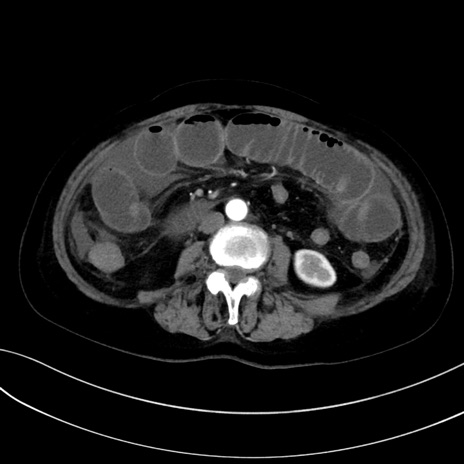

(冠状断像)1日半後